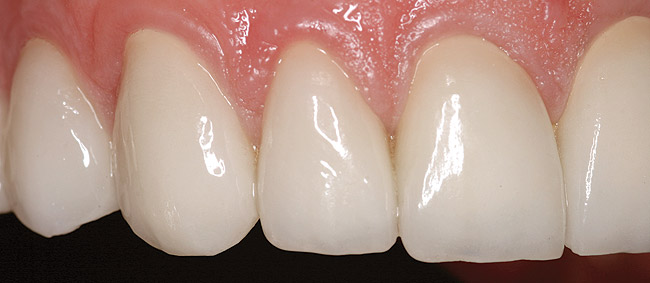

Figure 16 and Figure 17 An example of properly contoured anterior restorations. Notice the convex profile, natural drape of the lip, and point of interaction with the lower lip.

Figure 16

Figure 17